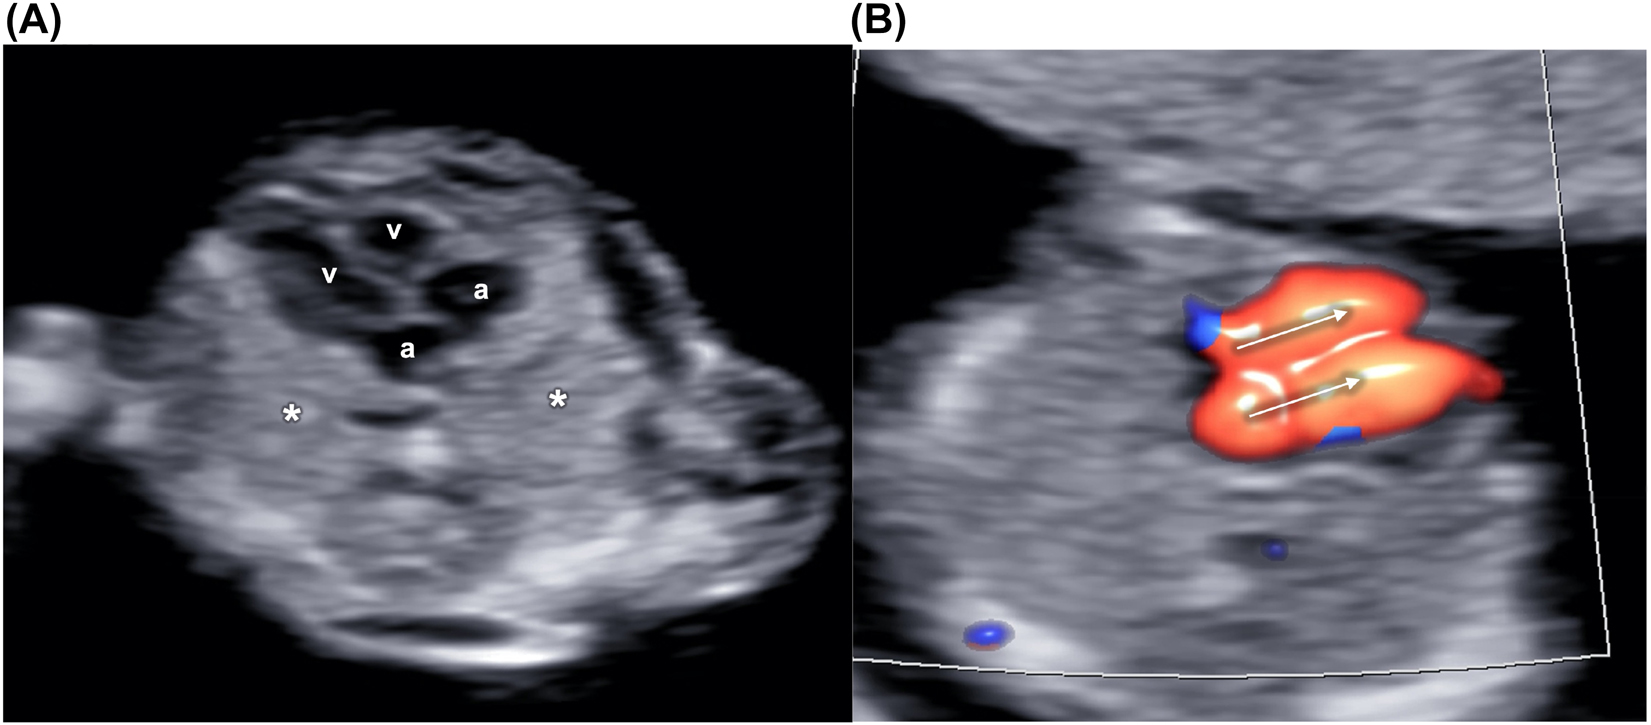

Grayscale image of the fetal heart and thorax.

The lung fields are visible on the sides of the heart, showing four balanced chambers, two atria (A) and two ventricles (v) (B) The atrioventricular flows (arrows) are highlighted by color Doppler on a four-chambers view.

The fetal heart lies in the middle of the fetal chest, occupying about one third of it, with the apex pointing towards the left side and with two thirds of its area on the left of the thoracic midline. The four chambers should be balanced in size, with the ventricles mildly bigger than the atria (Figure 6). The great arteries are similar in size but showing opposite direction (crossover of the outflow tracts). The aorta arises from the left ventricle and points to the right and the pulmonary artery from the right ventricle but with an anteroposterior direction, roughly parallel to the midline. The aortic and ductal arches could be visualized just above the outflow tracts joining just before and to the left of the fetal spine (Figure 7). At the same level, the superior vena cava could be possibly visualized in the context of a “3 vessel and trachea” view.

Aortic (A) and ductal (D) arches (V-shape) highlighted by color Doppler on a three vessels and trachea view.

The aortic arch is on the left of the trachea (T). Superior vena cava (C) is just on the right of the aorta (A).

Evaluating the four chambers view is recommended but limited to the visualization of four distinct chambers, looking balanced. Color Doppler could be useful to implement the visualization and the assessment of this view.

The visualization of the three-vessels or arches view (V-sign) on the axial plane by color Doppler is suggested but not mandatory in the first trimester.

To avoid oblique planes, the fetal heart should be observed on an axial view of the thorax, ideally including no more than one rib on each fetal side. The ultrasonic beam should be as parallel as possible to the ventricular septum (apical view) to optimize the visualization of the atrioventricular (AV) valves, allowing a better distinction of the four cardiac chambers. However, a transverse view of the heart could also be considered, with the ultrasound beam parallel to the ventricular and atrial septum, allowing better visualization of these structures, but often with a suboptimal visualization of the AV valves and a less clear distinction of the chambers. On an apical view, the heart rate could be calculated after sampling one of the AV valves, with a gate width of about 3 mm, and insonation angle ideally less than 30° from the ventricular septum.

The color Doppler could be helpful in case of limited visualization of the structures due to fetal or uterine unfavorable position, high maternal body mass index, or early gestational age. In addition, the Doppler signal allows distinguishing the atrioventricular flow through the mitral and tricuspid valves, providing information about the presence of balanced atria and ventricles, if the flow signals are similar in size, direction, and velocity, excluding significant valve regurgitation, critical stenosis or atresia.

The plane, including the arches, could be obtained starting from the four chambers apical view, sweeping the probe cranially. Such structures could be highlighted by color Doppler, which would appear similar in size and color in normal conditions.